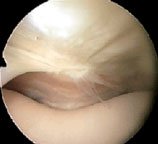

You will remember that so far I have taken you through the routine of starting with the arthroscope in the anterolateral portal (AL) and examining the medial side (as in the photo), then swapping it over to the anteromedial portal (AM) and examining the lateral side (link). From these two portals, much of the knee cavity can be viewed and probed.

Here the arthroscope has been withdrawn above the level of the medial plica to reveal the suprapatellar plica (black arrow). You can see its position in relation to the medial plica (white arrow), which is just draping itself out of sight over the front of the femur. REMEMBER, WE ARE LOOKING FROM ABOVE, WITH THE SCOPE IS THE LARGE CAVITY ABOVE THE PATELLA. You can't see this structure from the ordinary portals!